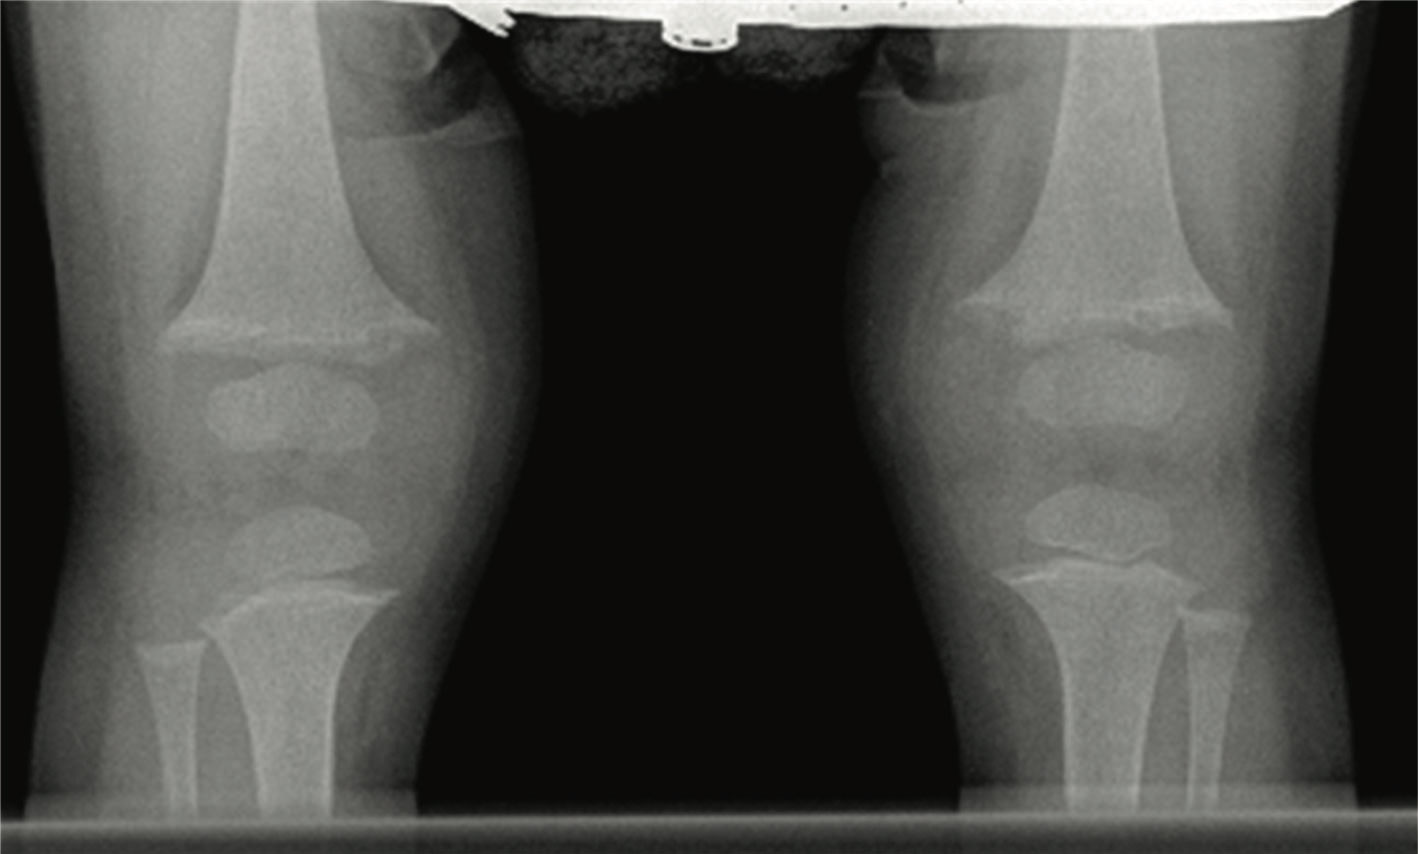

Radiographic studies of knee and wrist joints are showed in the upper figure. She was treated with ergocalciferol at various doses for 2 years with no improvement. Her serum 25 hydroxy vitamin D increased from 22 ng/mL at baseline to 80 ng/mL after a megadose of ergocalciferol. Repeat radiographs of her knees at age 3 years showed increased widening of epiphyses with increased cupping and fraying of the metaphyses (lower figure). She had complaints of polyuria, polydipsia, enuresis, and bone pain.